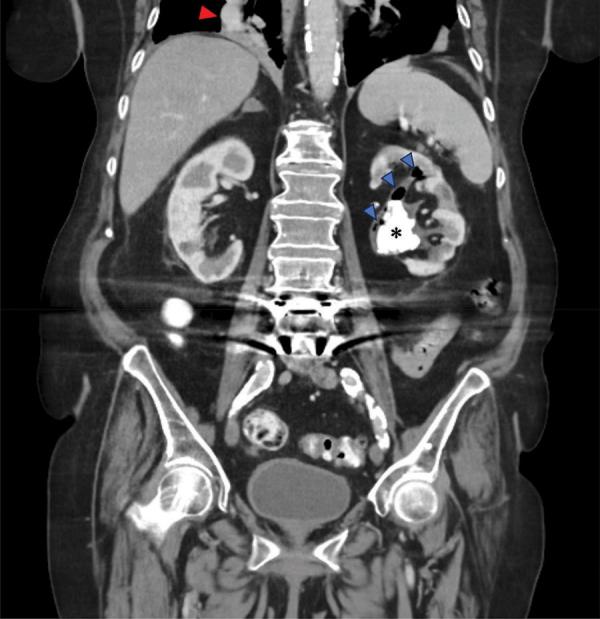

Xanthogranulomatous and Emphysematous Pyelonephritis: Two Rare Entities Occurring in One Kidney.

Both xanthogranulomatous and emphysematous pyelonephritis are severe renal inflammatory disorders, occurring simultaneously in extremely rare cases.